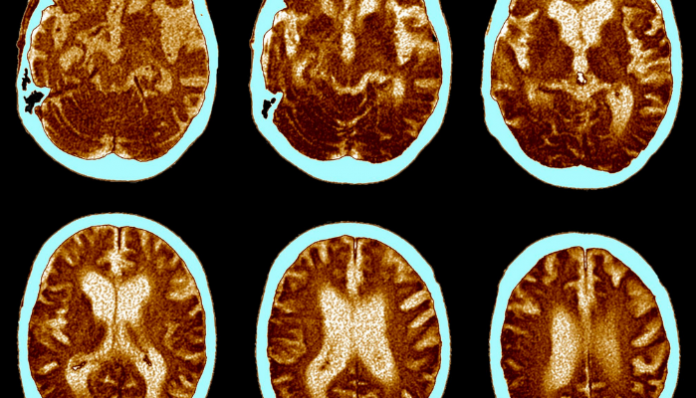

Uno de los primeros signos posibles de la enfermedad de Alzheimer es el deterioro cognitivo leve (DCL), que es la etapa entre el deterioro cognitivo esperado del envejecimiento normal y la demencia. Según una investigación anterior, la resonancia magnética funcional (fMRI) se puede utilizar para identificar las regiones del cerebro que pueden estar asociadas con la aparición de la enfermedad de Alzheimer, según Maskeliunas. Las primeras etapas de DCL a menudo casi no tienen síntomas claros, pero en bastantes casos pueden detectarse mediante neuroimágenes.

El modelo basado en el aprendizaje profundo se desarrolló como una fructífera colaboración de los principales investigadores lituanos en el sector de la inteligencia artificial, utilizando una modificación de ResNet 18 bien afinado (red neuronal residual) para clasificar las imágenes de resonancia magnética funcional obtenidas de 138 sujetos. Las imágenes se dividieron en seis categorías diferentes: desde saludables hasta el espectro del deterioro cognitivo leve (DCL) hasta la enfermedad de Alzheimer. En total, se seleccionaron 51,443 y 27,310 imágenes del conjunto de datos de resonancia magnética funcional de la Iniciativa de neuroimagen de la enfermedad de alzhéimer para entrenamiento y validación.

Según el profesor Rytis Maskeliunas, de la Facultad de Informática de KTU, el modelo pudo encontrar de manera efectiva las características de MCI en el conjunto de datos dado, logrando la mejor precisión de clasificación del 99,99 por ciento, 99,95 por ciento y 99,95 por ciento para MCI temprano, frente a AD, MCI tardío frente a AD, y MCI frente a MCI temprano, respectivamente.